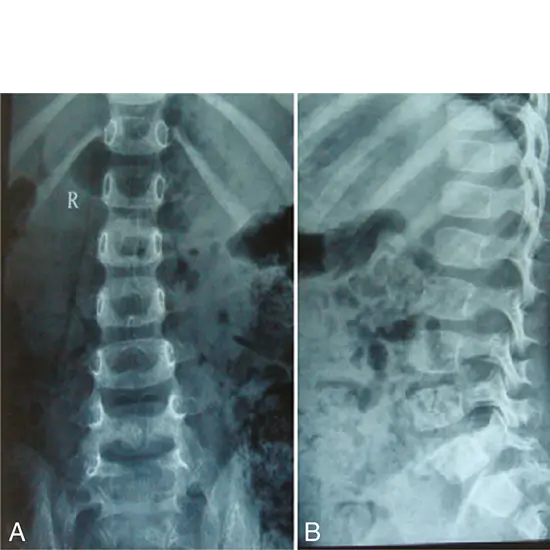

What is an X-ray Dorso Lumbar Spine LAT View Test?

The Lumbar Vertebrae are the bottom five vertebrae. This lower back area causes most backaches. Recurrent back pain prompts a doctor to order an X-ray.

The X-ray will indicate any abnormalities, traumas, fractures, or suspected disc issues such as spondylolisthesis and arthritis causing the symptoms. Additional testing may be required for a comprehensive diagnosis if a problem is identified.